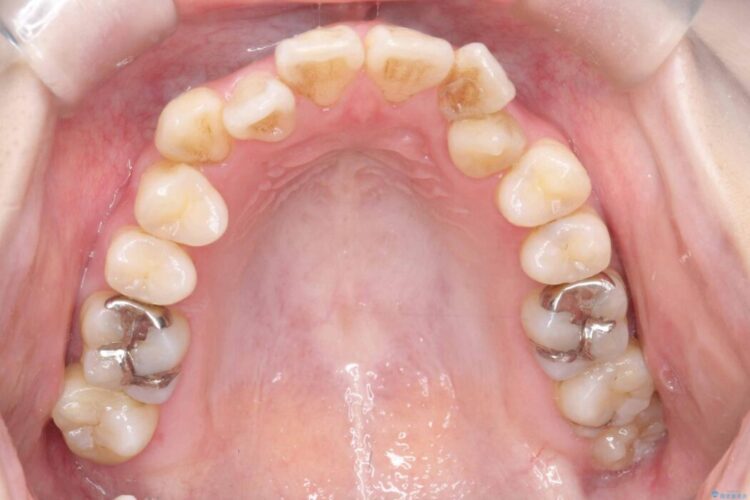

開咬、叢生、八重歯が気になるとご来院された患者様です。

精密検査の結果、上顎左右4番および下顎左右5番の計4本を抜歯し、目立ちにくいクリア装置にて治療を行いました。

また、虫歯があったので、矯正開始前に虫歯治療を行っております。